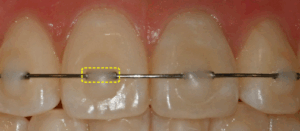

망우동 치과 앞니 부분교정 미니튜브(MTA), 짧은 기간 안에 자연스러운 미소 완성하기

안녕하세요, 망우동 치과 김정은 원장입니다. 혹시 사진을 찍을 때 무의식적으로 입을 다물게 되시나요? 또는 거울을 볼 때마다 삐뚤어진 앞니 때문에 웃음이 어색해지는 경험, 많은 분들이 공감하실 겁니다. 다행히 눈에 잘…